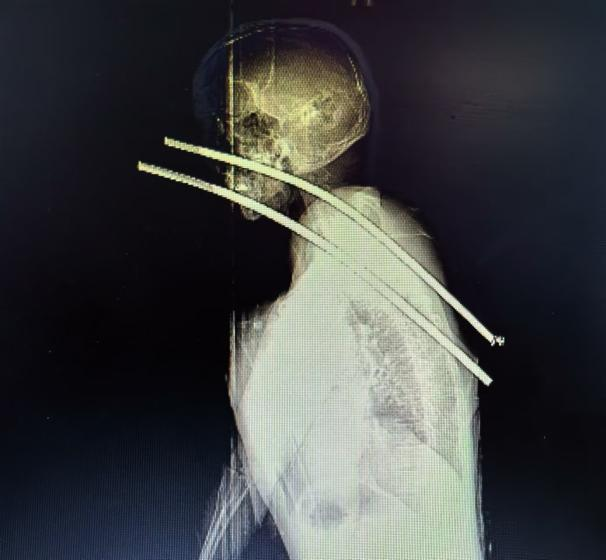

救护车呼啸而归,看到被送达抢救室的患者,现场的医护人员都倒吸了一口凉气——两根钢筋分别从左侧颈部及右侧口腔颌面部刺入,穿出后至后胸背皮下颈部,还有长长的一截露在外面。场面触目惊心,抢救也立即展开。

迅速做好术前准备,患者送达手术室,各科室各司其职,配合默契。手术过程顺利,先沿右锁骨表面作切口,然后小心翼翼地逐层解剖,切开钢筋周围的肌肉组织结构,松解钢筋和骨头间的间隙,分离血管和神经,一步步探查伤口的情况,显露出钢筋后,缓慢将钢筋拔除。术后患者转回急诊重症监护室进一步治疗。